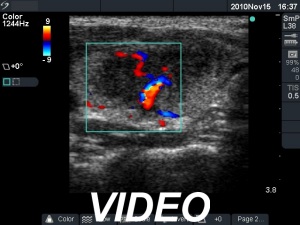

Initial examination (first row of images):

Ultrasonography: The right thyroid was echonormal and contained several small, insignificant lesions. There was a hypoechogenic lesion with blurred borders in the central and in the ventro-medial part of the left thyroid with increased intranodular blood flow.

The ultrasound pattern of de Quervain's thyroiditis and that of papillary cancer are very similar: a hypoechogenic lesion with blurred borders are found in both cases. They differ in vascularization statistically but the vascular pattern has only limited practical significance. In the acute phase of de Quervain's thyroiditis the vascularization is generally decreased but even in this case the situation was the opposite. The finding of not one but multiple hypoechogenic areas favored the possibility of subacute thyroiditis.